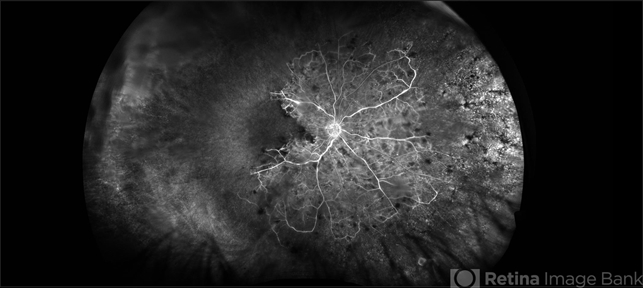

- central retinal vein occlusion (CRVO), ischemic CRVO, sclerotic vessels, attenuated vessels, hemorrhage

- 76-year-old woman with an ischemic central retinal vein occlusion, severely attenuated and sclerotic vessels and scattered retinal hemorrhages. Vision decrease over 1 year. VA 20/CF. Patient is returning for pan retinal photocoagulation.